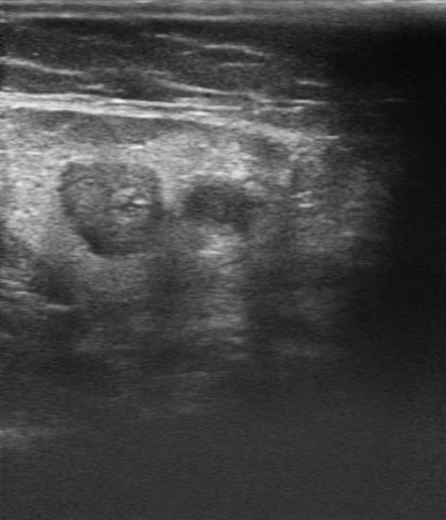

Buen estado general. Consciente y orientado en las 3 esferas. Bien perfundido. Eupneico en reposo. Auscultación cardiopulmonar: rítmica con murmullo vesicular conservado. En cara interna de miembro inferior izquierdo, zona eritematosa y ligeramente edematosa con palpación de trayecto endurecido de territorio de vena safena interna. Varices bilaterales (Imagen 1).

Ecografía de miembro inferior izquierdo: contenido hiperecogénico en todo el trayecto de la vena safena interna, no compresible. Sistema venoso profundo permeable sin datos de TVP (Imagen 2,3,4).